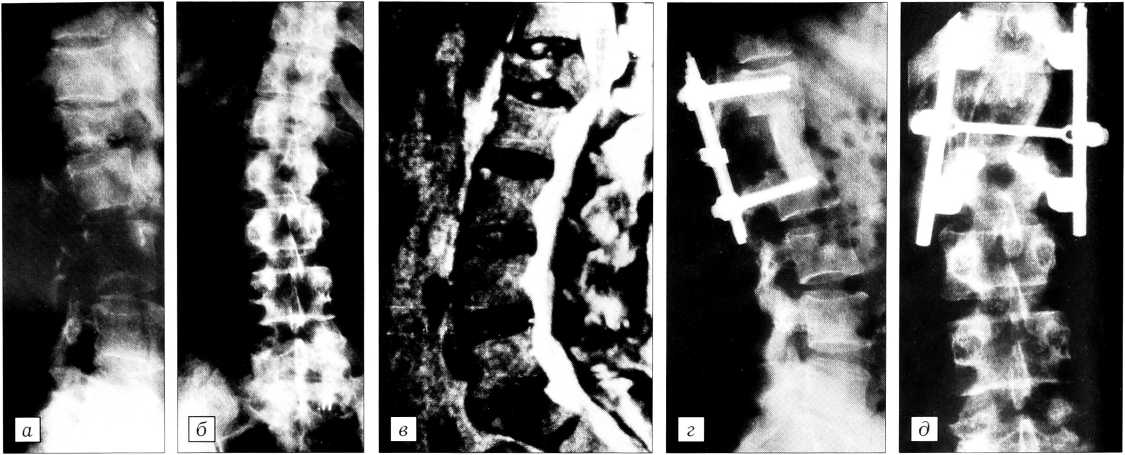

Рис. 1. Больной М. 19 лет. Последствия тяжелой позвоночно-спинномозговой травмы: консолидированный боковой переломовывих Т7-8, анатомический перерыв спинного мозга, ламинэктомический дефект дуг Т6-8 позвонков, металлический имплантат (типа mesh) в длинных мышцах спины, нижняя спастическая параплегия, нарушение функции тазовых органов по центральному типу.

Боковая спондилограмма (а) и компьютерная томограмма (б) до оперативного лечения; боковая (в) и переднезадняя (г) спондилограммы после выполнения резекции тел Т7, Т8 позвонков, передней декомпрессии содержимого дурального мешка, резекции суставных и поперечных отростков, головок ребер на уровне Т6-8 позвонков, ревизии спинного мозга, менингорадикулолиза, переднего комбинированного (кость и биоситалл) спондилодеза, передней и задней коррекции и фиксации позвоночника Z-пластиной, дистрактором и контрактором.